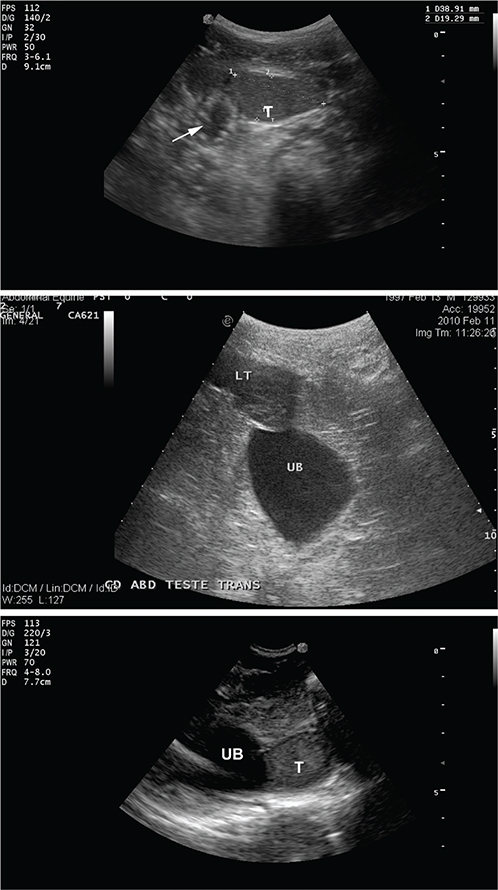

Abdominal testes are often visualized on the ventral abdominal wall within a few centimeters of or adjacent to the urinary bladder (Figures 17, 18) and lying between the intestinal loops or colon haustra. Left abdominal testis are more difficult to visualize. They may be found between the left ventral colon and the spleen. Other factors that may hinder visualization of the abdominal testes include higher location due to short testicular cord, gas, or food-filled large colon. Examination of the horse after a period of 24 to 36 hours fasting may improve ultrasonographic localization of the abdominal testis.104

Fig. 17.

Figure 17. Ultrasonogram of abdominal testis testis (T) showing clearly an anechoic area corresponding to the central vein (top arrow), and a teratoma.

Fig. 18.

Figure 18. Examples of ultrasonograms of abdominal testes visualized by abdominal scanning (T = testis, UB = urinary bladder, arrow indicates intestinal loops).

The combination of inguinal and abdominal ultrasonographic examination allow location of the testes with very high sensitivity (97.6%) and specificity (100%).104,111 However, some authors reported only a 50% localization of incomplete abdominal testis with a specificity of 75%.109 Other authors reported localization of the abdominal testis in 72.7% of the cases.108 This difference of results may be due to a difference in experience and/or type of horses examined, gas or content in the large colon.